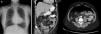

The patient is a 57-year-old woman under treatment with APC (Argon ERBE APC-300) due to gastric and duodenal angiodysplasias secondary to Rendu–Osler–Weber disease. After one session, she came to the emergency room with abdominal distension and epigastric pain that had been progressing for 12h. The patient presented a distended abdomen that was slightly painful, with no signs of peritoneal irritation. Chest radiograph revealed a massive pneumoperitoneum (Fig. 1). Triple-contrast CT detected abundant pneumoperitoneum with no free fluid; no area of dehiscence was observed, and there was no extravasation of water-soluble oral contrast (Fig. 1). While in the emergency department, a series of analyses showed no elevated acute-phase reactants, and the patient remained asymptomatic. In view of the clinical–analytical–radiological findings, we decided on observation and conservative management with nil per os, a nasogastric tube and iv ertapenem 1g/24h. No complications were observed during hospitalization, and the patient was discharged after 6 days. After discharge, a clinical-radiological follow-up showed a gradual reduction of the intra-abdominal air volume (Fig. 2).